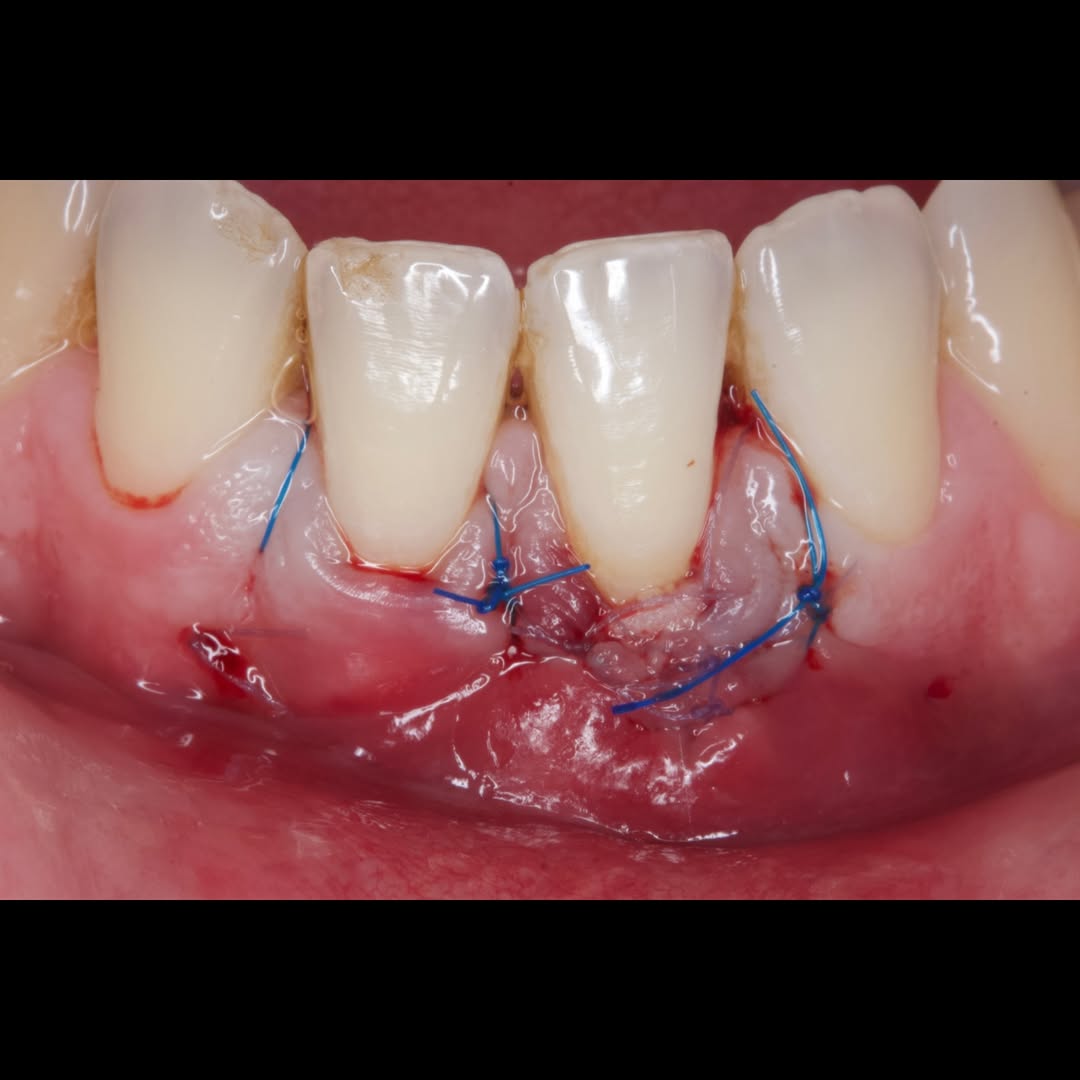

Durante una mañana, asistirás a una Cirugía Mucogingival de recubrimiento radicular de recesiones múltiples en IV y V sextante (36 a 43).

Gracias al uso del microscopio y a la proyección en tiempo real en pantalla, verás exactamente lo mismo que veo yo durante la cirugía, sin tener que estar

Podrás asistir a la planificación de casos y cirugía de injerto de tejido conectivo. Factores determinantes y elección de la técnica adecuada. Sumérgete en un protocolo predecible y técnicamente correcto para obtener resultados óptimos.

Aprende la planificación y técnica de la cirugía Mucogingival para el recubrimiento de recesiones y aumento de banda queratinizada en el sector anteroinferior

La formación comenzará con la presentación del caso clínico que se abordará durante el curso, seguida de una cirugía en directo, que permitirá observar paso a paso el procedimiento y la toma de decisiones clínicas. Durante la jornada se profundizará en los conceptos biológicos aplicados a

Durante una mañana, asistirás a una Cirugía Mucogingival de recubrimiento radicular de una recesión unitaria en 31 con frenillo asociado. Gracias al uso del microscopio y a la proyección en tiempo real en pantalla, verás exactamente lo mismo que veo yo durante la cirugía, sin tener que estar

Una estancia clínica pensada para quienes quieran iniciarse o dar un paso más en el campo de la cirugía mucogingival. Durante esta experiencia tendrás la oportunidad de aprender en directo cómo se planifica y se lleva a cabo una cirugía mucogingival mediante técnica de Túnel.

Formación teórico-práctica completa sobre las técnicas más avanzadas en cirugía mucogingival. Durante dos días intensivos, los participantes aprenderán desde la evidencia científica y la anatomía de las zonas donantes hasta la ejecución de injertos, cubrimiento radicular y aumento de